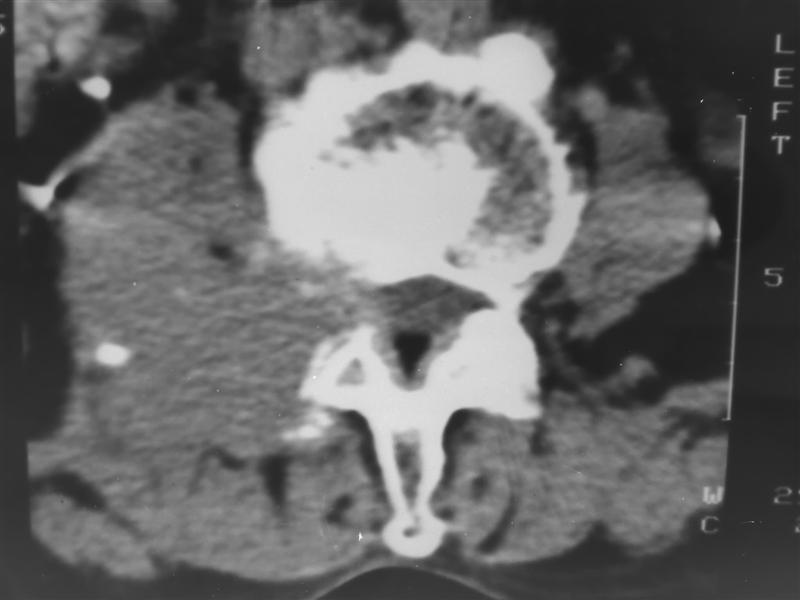

以下是引用guzhongliangddd在2007-9-27 13:42:00的发言:[br]首先考虑是转移性肿瘤.

以下是引用老爱克斯新网客在2007-9-27 17:59:00的发言:[br]多个椎体及椎弓跟骨质破坏,并见软组织肿块,符合转移瘤改变,

以下是引用wqs571018在2007-9-27 16:48:00的发言:[br]支持:多发病变,骨质破坏伴软组织块影,符合转移.